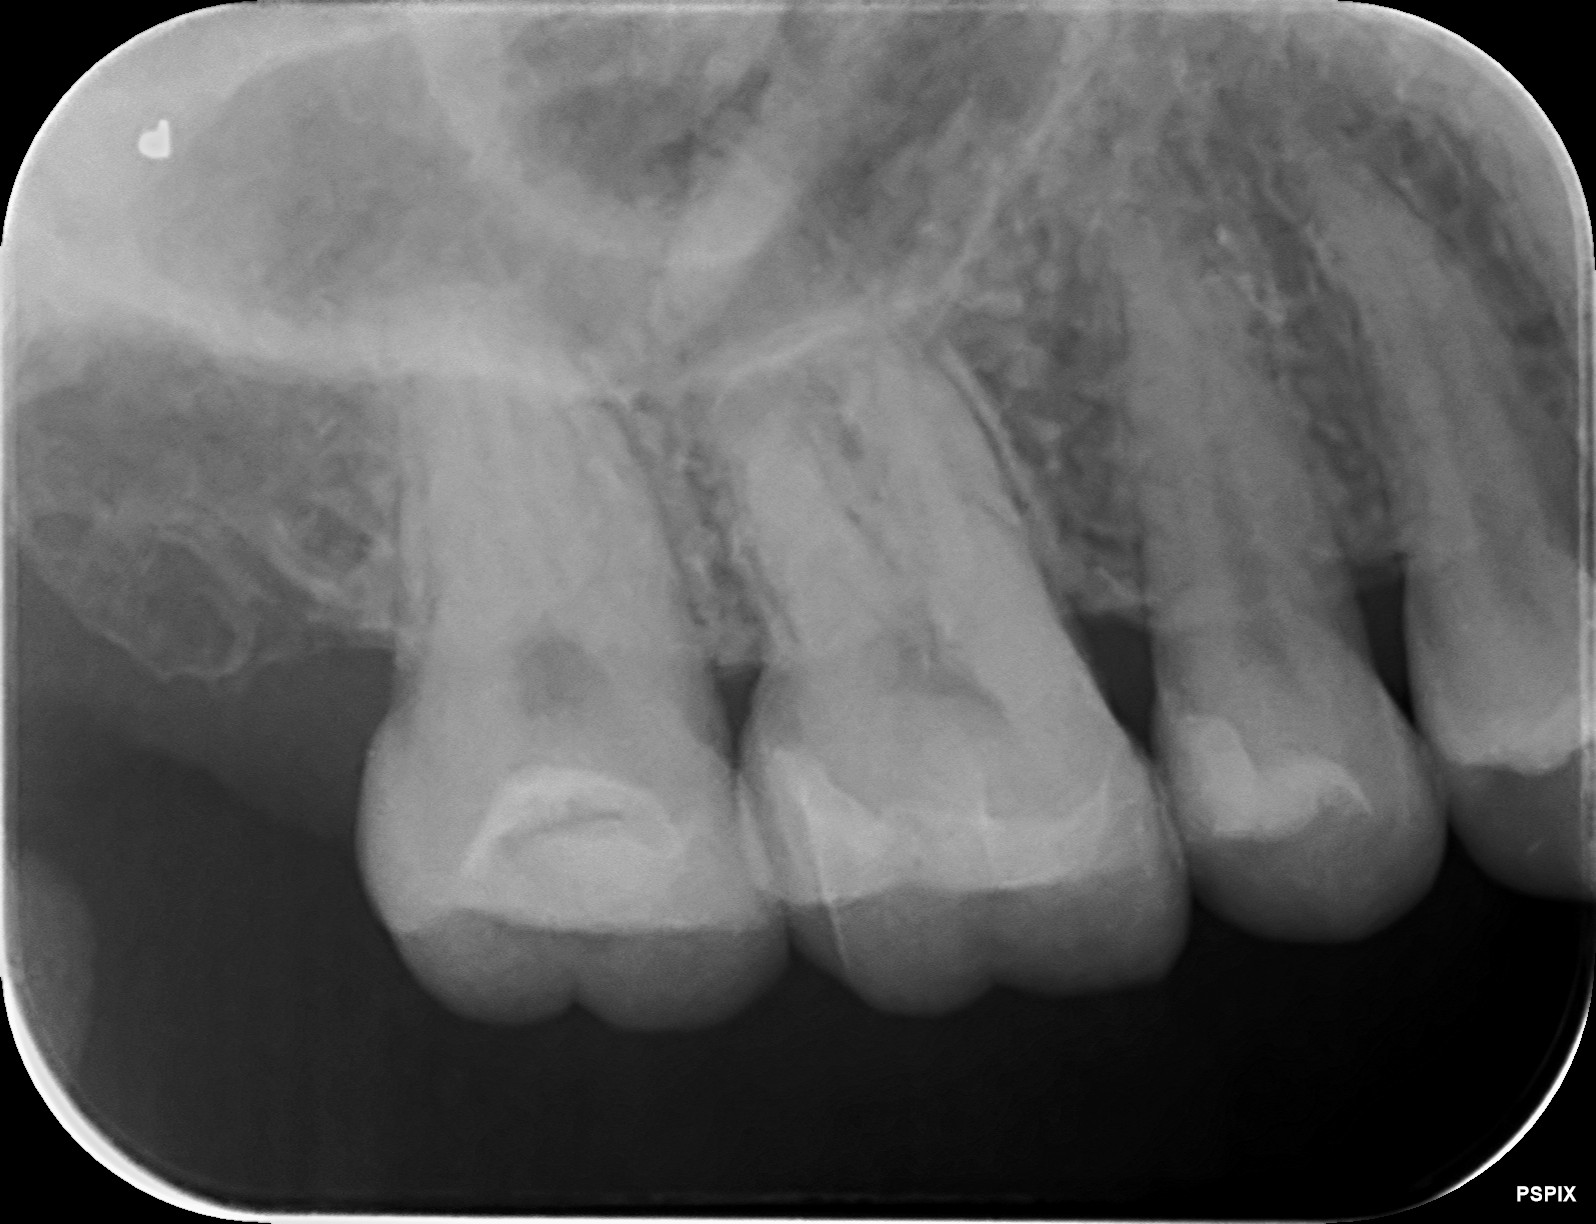

ゴールドインレー(金合金)が虫歯?その原因は?